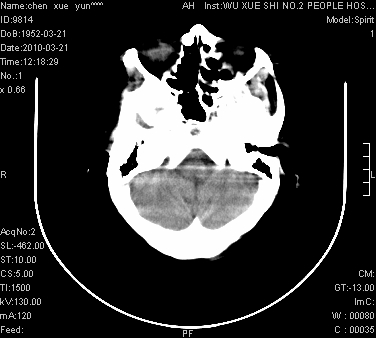

性别:不详;年龄:58岁;病史:不详。

ct表现:1、右侧额颞叶深部不规则钙化密度团块,呈弯曲条带状,占位效应不明显,考虑少枝胶质细胞瘤可能性大于血管瘤。2、右枕叶大片不规则低密度影,密度近似于脑脊液,右侧侧脑室后角及三角区扩张,考虑为陈旧性脑梗塞。

讨论:1、这个病灶的钙化有点像脑回样钙化,因此我最初考虑颅面血管瘤病(sturge-weber综合征),但是查阅了我们网站上的几个颅面血管瘤病病例,钙化均位于脑实质表面,沿脑回分布,而这例病灶位置较深,因此可以否定“颅面血管瘤病”这个诊断。

2、卜一会员曾经说过:少枝胶质细胞瘤的典型征象为弯曲条带状钙化,可作为定性的可靠征象(http://www.radida.com/news_view.asp?id=5150)

3、血管瘤也可以出现弯曲条带状钙化,但血管瘤多数出现“负占位”效应,即病灶周围的脑室、脑池及脑沟不是受压变窄,而是局限性的增宽。